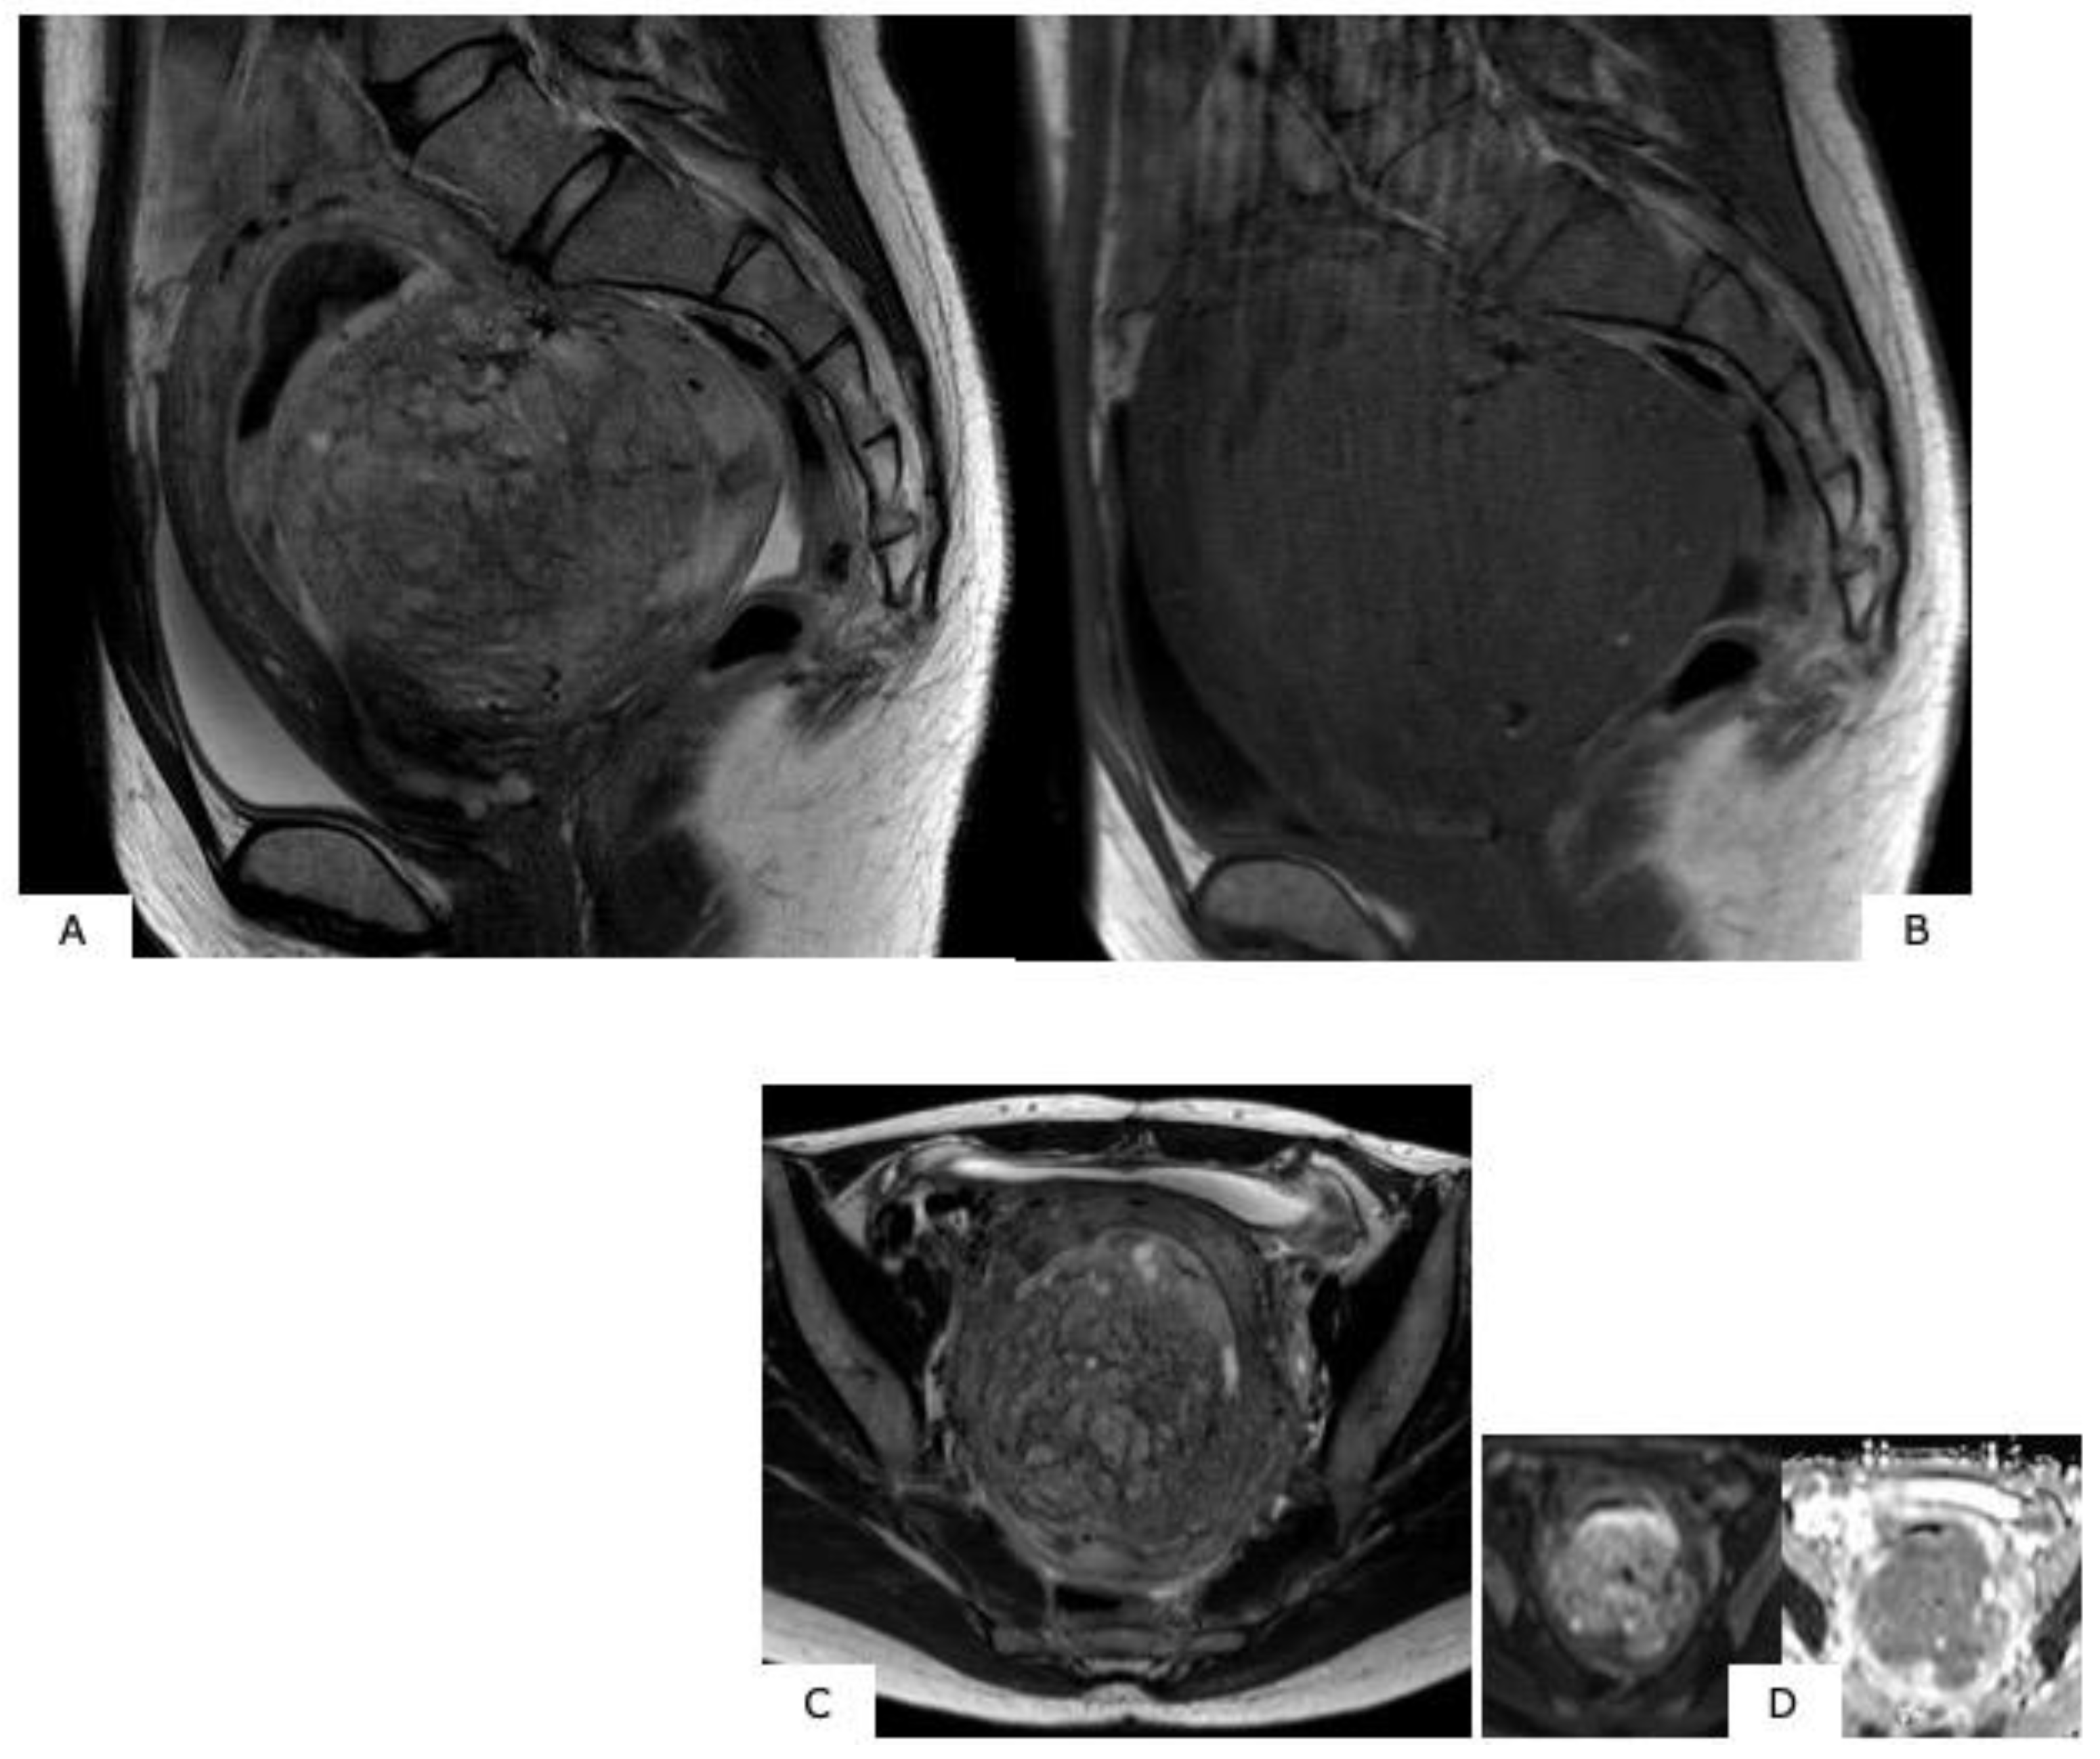

- Ascertain the contrast effect of the mass. While sarcoma shows a strong contrast effect from an early stage, in some cases, the contrast effect is insufficient, with an area presumed to be necrosis [4].

6.2. Leiomyosarcoma

7. Differentiating between Uterine Myoma and Sarcoma